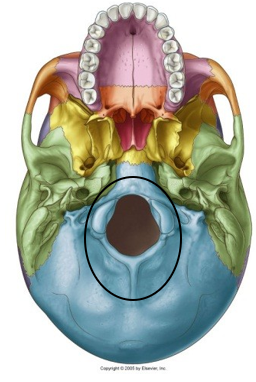

• Ring Fracture

•Caused by skull being forced down onto the vertebral  column

–Fall onto head from height

–Fall onto locked legs or buttocks

•Fracture begins at posterior occipital and progresses  anteriorly

–Mild force only affects occipital

–Severe force results in complete ring fracture